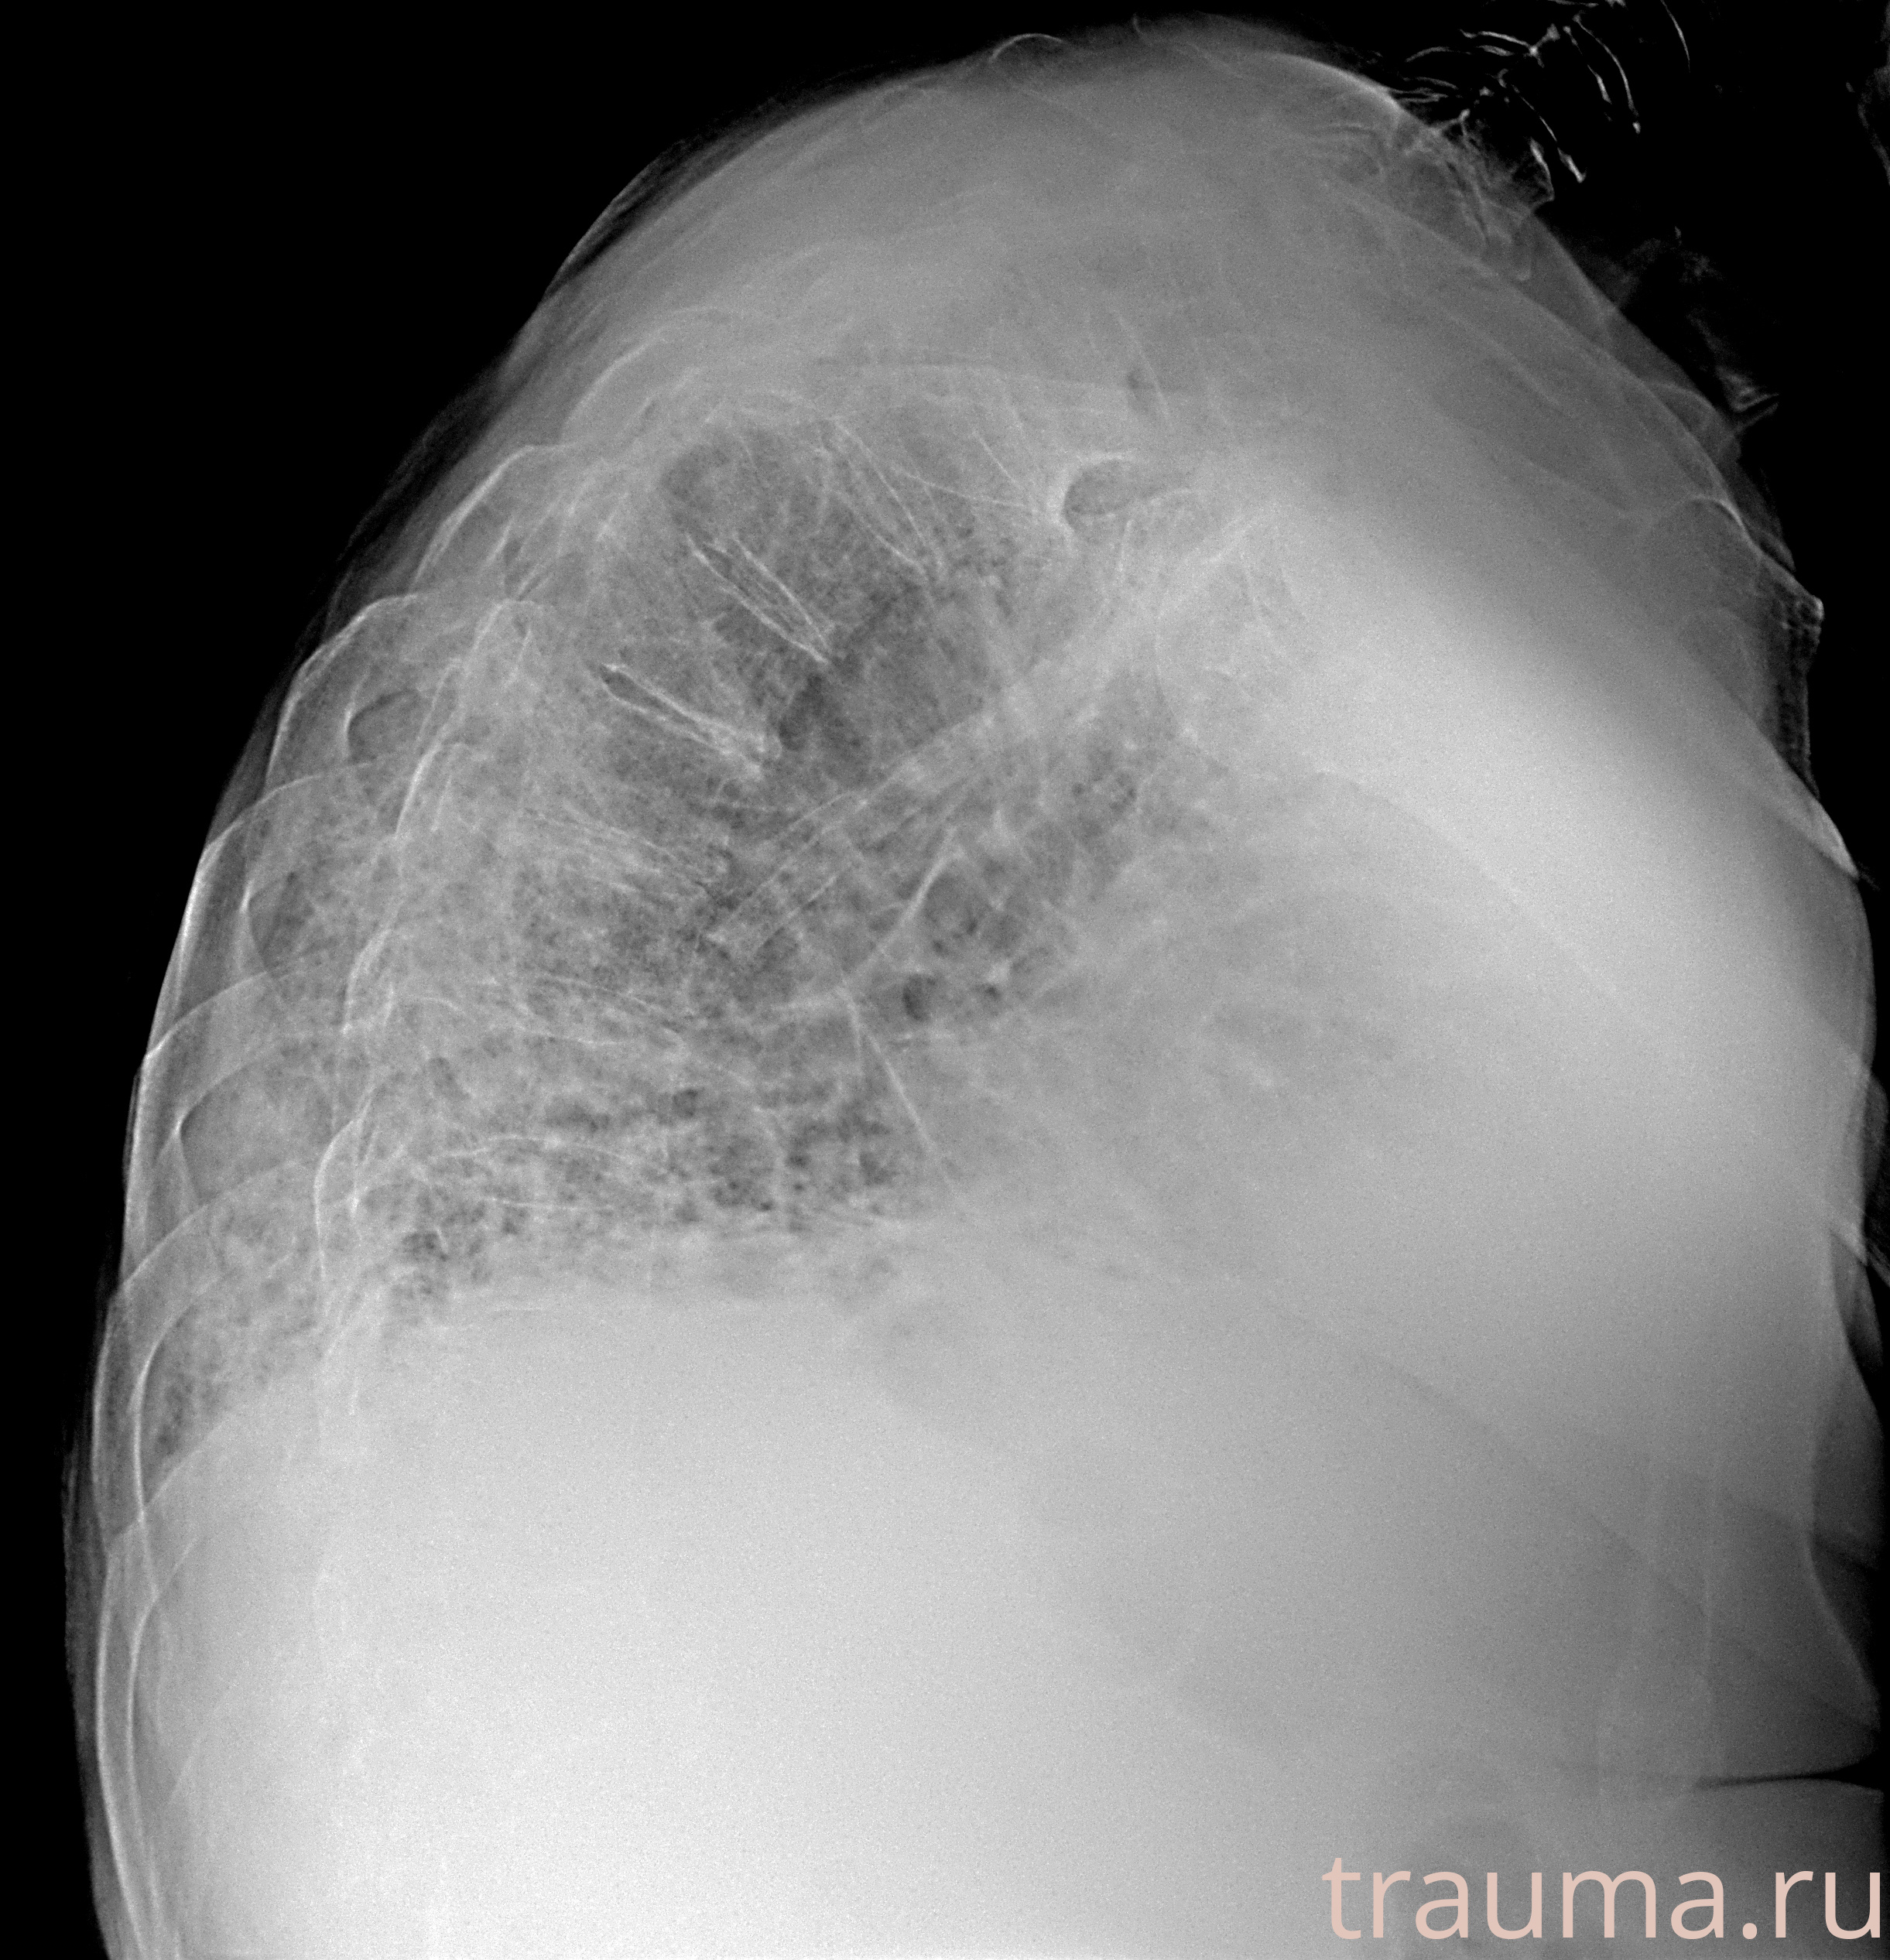

Рентген на дому: по вашему адресу приезжает врач-рентгенолог, травматолог-ортопед с мобильным рентгеновским аппаратом, проводит диагностику травмы или заболевания, делает необходимые рентгенограммы, дает рекомендации по дальнейшему лечению. Получить качественные снимки в домашних условиях возможно благодаря уникальной методике, разработанной МосРентген Центром для института  Склифосовского

при переломе шейки бедра и пневмонии от компании МосРентген Центр - партнера Института имени Склифосовского